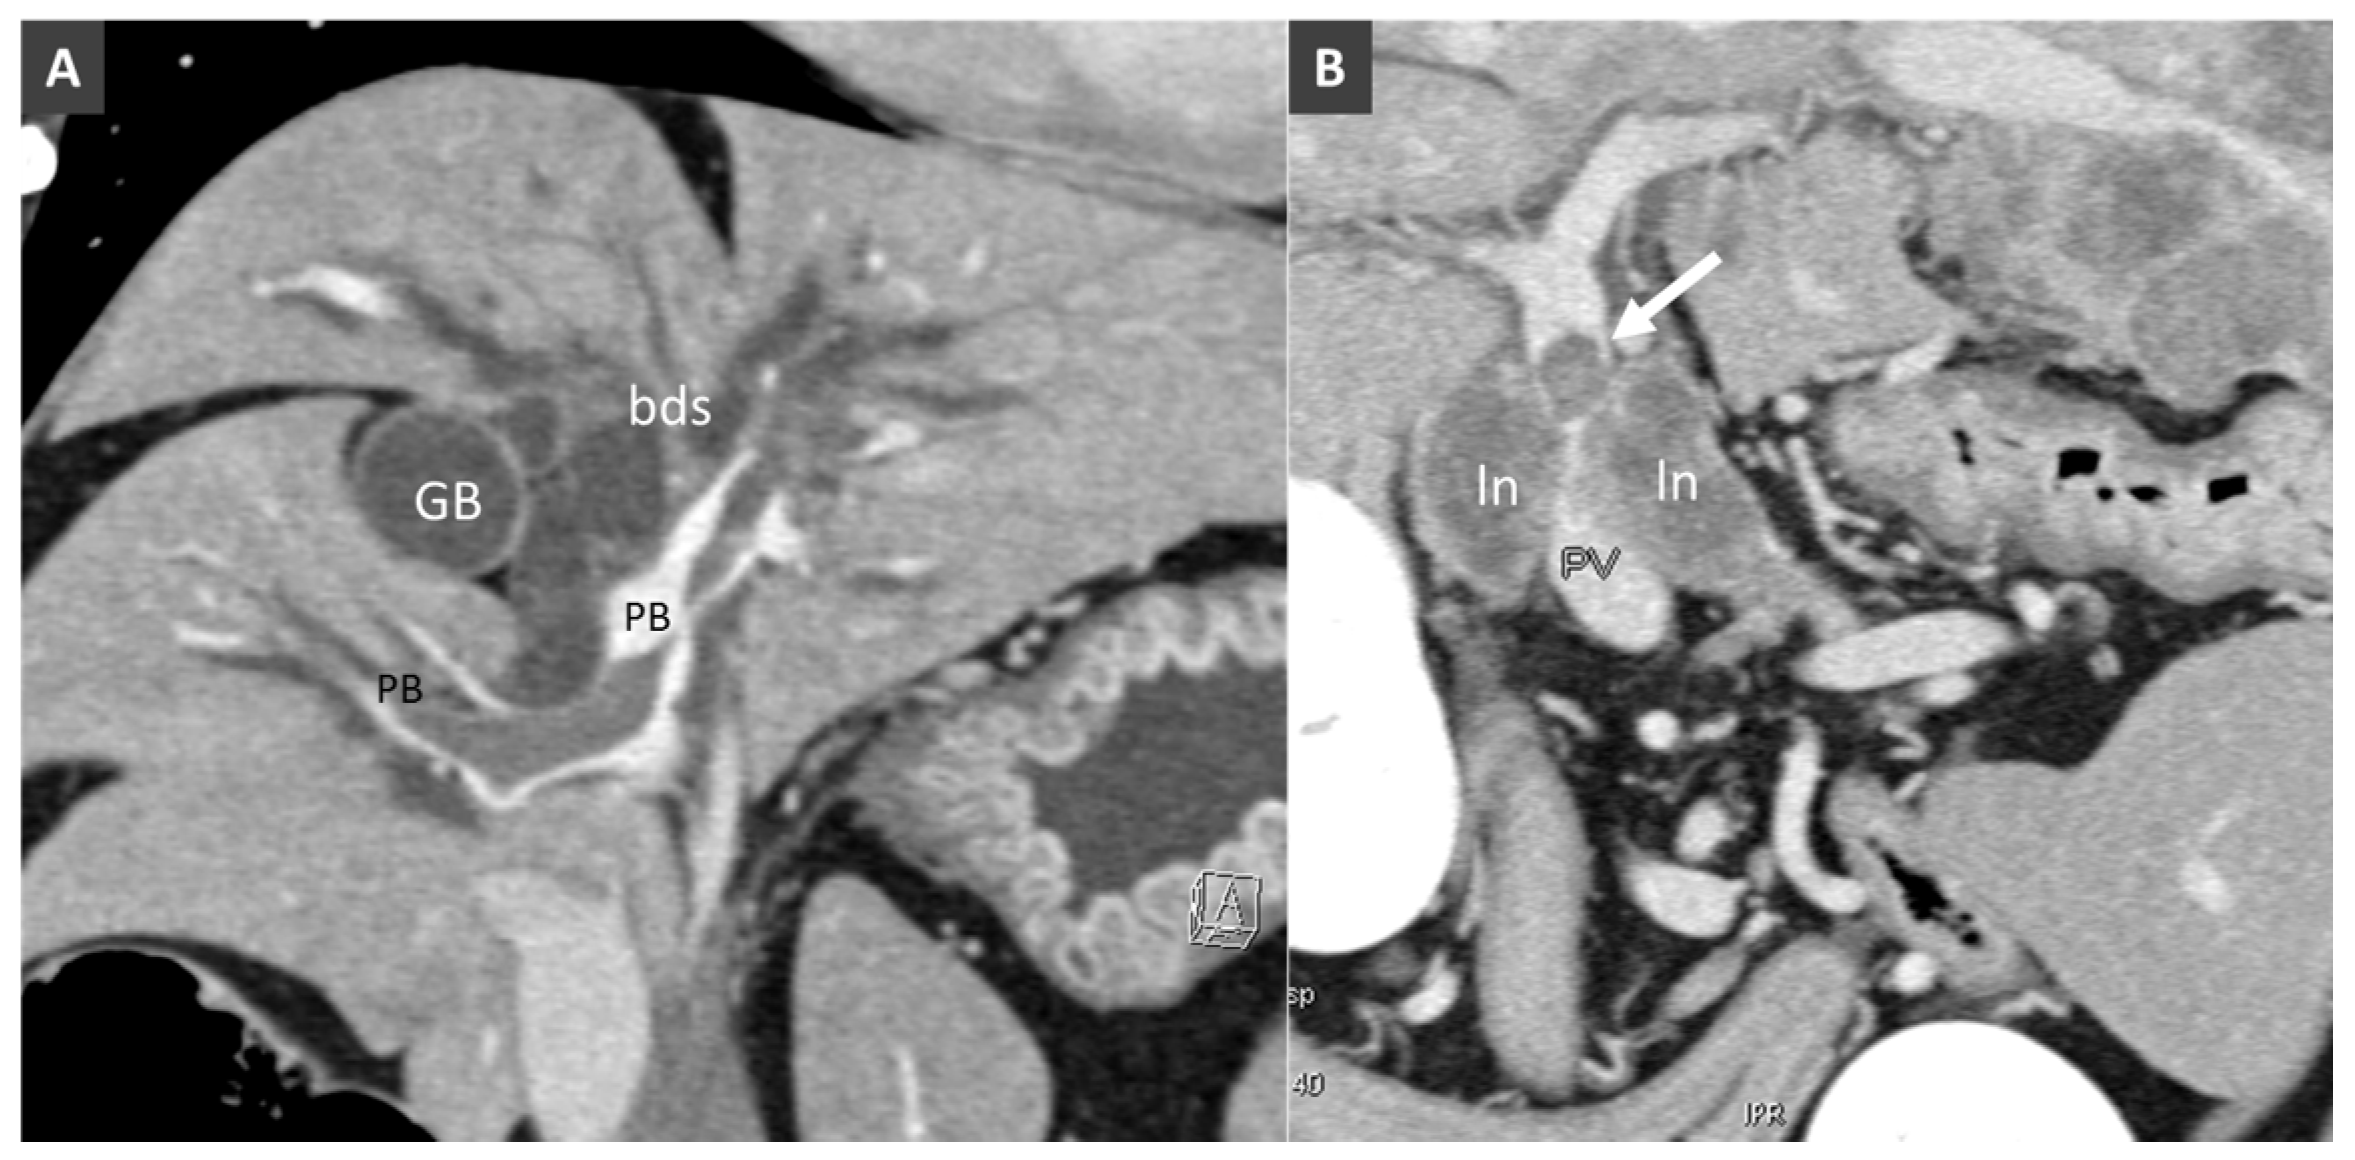

- Specchi, S.; Pey, P.; Ledda, G.; Lustgarten, M.; Thrall, D.; Bertolini, G. Computed tomographic and ultrasonographic characteristics of cavernous transformation of the obstructed portal vein in small animals. Vet. Radiol. Ultrasound 2015, 56, 511–519. [Google Scholar] [CrossRef] [PubMed]